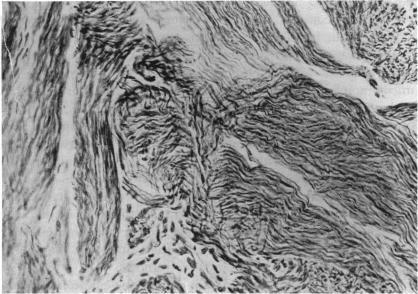

BRALEY A E

Trans Am Ophthalmol Soc. 1954;52:189-97.